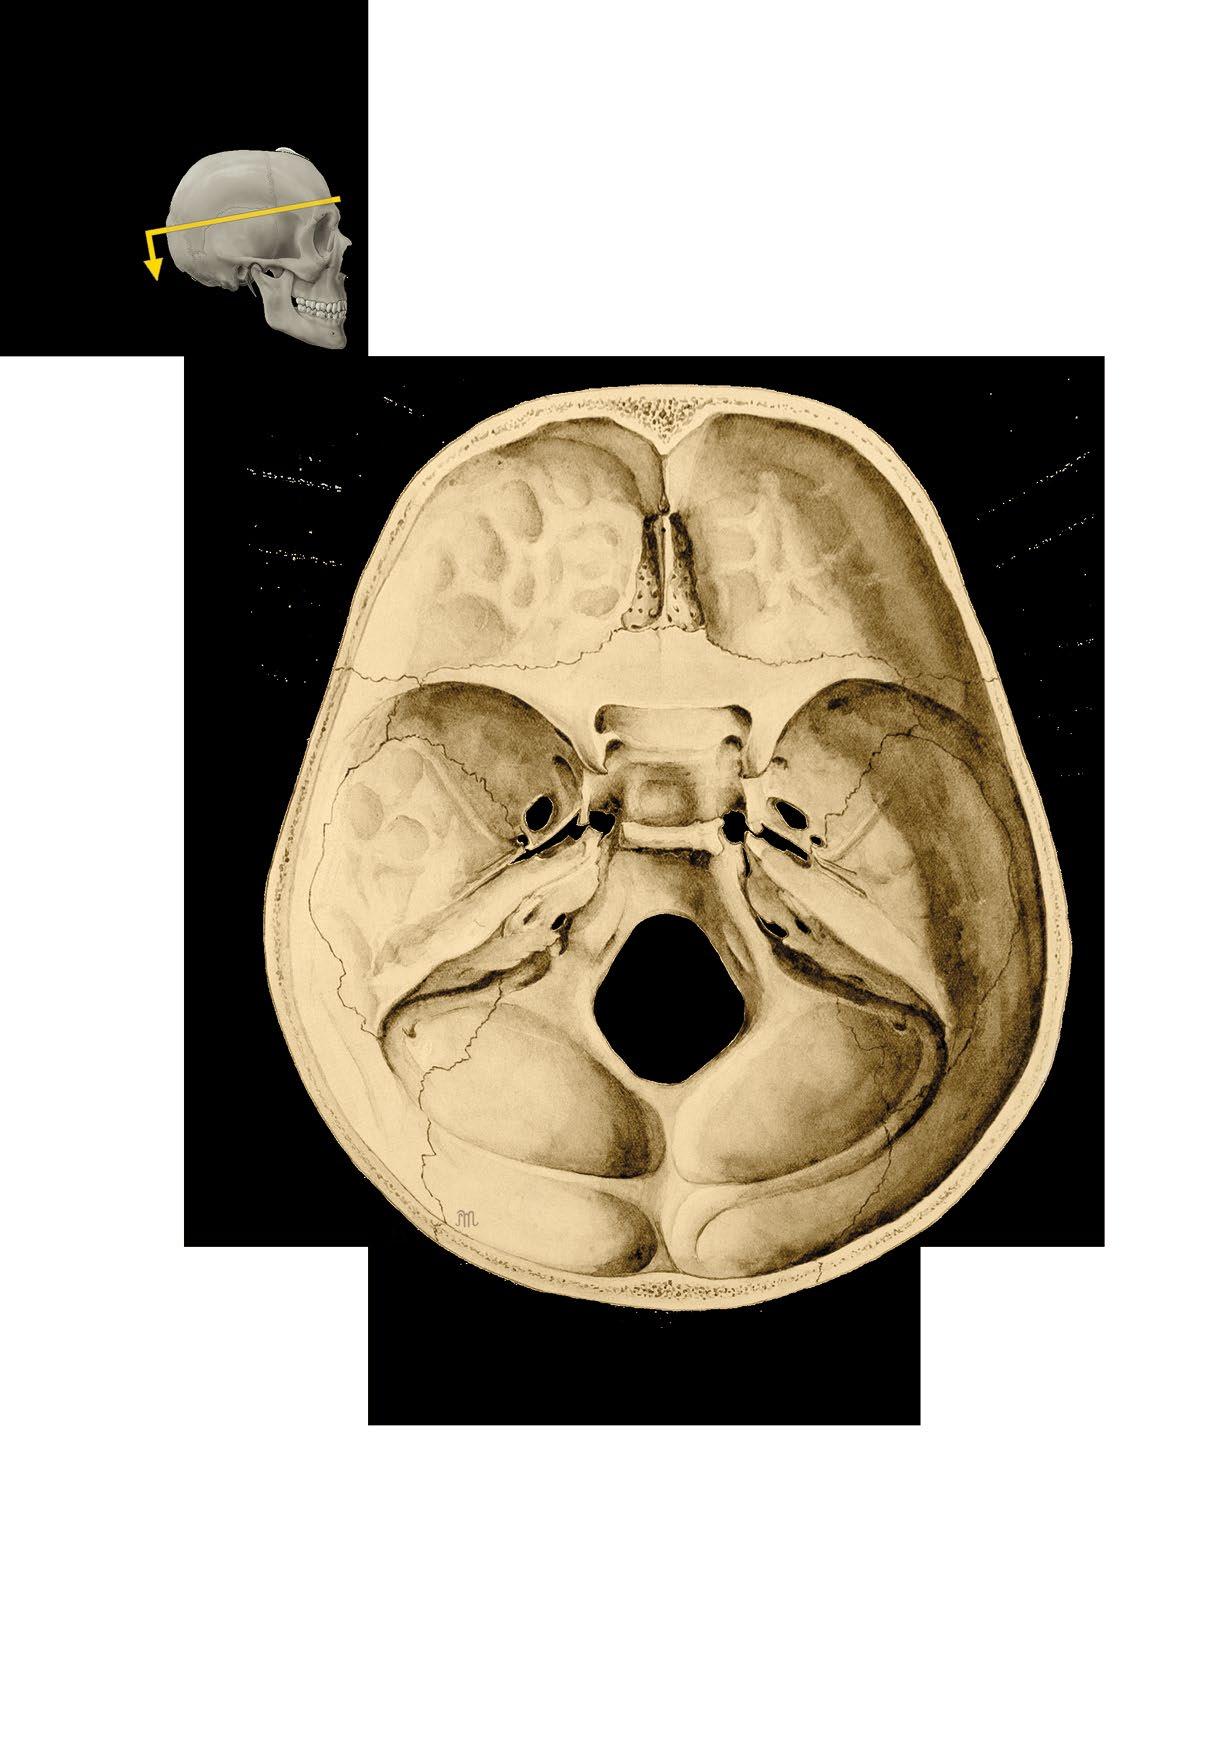

Basis cranii externa et interna

b vnitřní plocha base lební

c členění vnitřní plochy base

fossa cranii posterior

External and internal base of the skull

a external surface

b internal surface c cranial fossae

canalis opticus impressiones gyrorum foramen rotundum

ala major

foramen ovale

foramen lacerum

foramen spinosum

apertura interna canalis carotici

meatus acusticus internus

foramen jugulare

canalis nervi hypoglossi

foramen magnum

pars orbitalis ossis frontalis ala minor

sulcus praechiasmaticus

processus clinoideus anterior

fossa hypophysialis processus clinoideus posterior

clivus dorsum sellae

margo superior partis petrosae

sulcus sinus sigmoidei

sulcus sinus transversi

fossa cerebellaris

protuberantia occipitalis interna

fossa cerebralis

Basis cranii interna, vnitřní plocha spodiny lebeční

Internal surface of the base of the skull